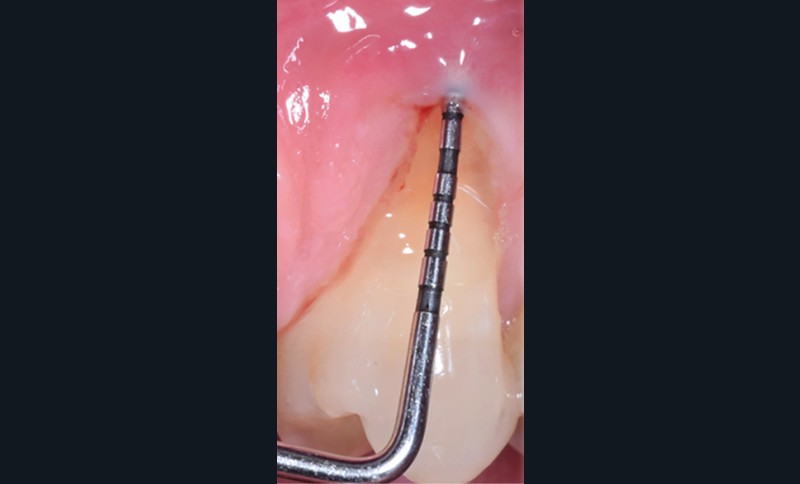

Dans un contexte parodontal sain, le principal facteur de risque à identifier avant un traitement orthodontique est le phénotype parodontal fin. L’examen clinique se réalise à l’aide d’une sonde parodontale graduée. Celle-ci est visible par transparence lors de son insertion dans le sulcus (fig. 1). D’un point de vue clinique, il est important de remarquer qu’il peut exister des différences d’épaisseur et de hauteur des tissus kératinisés (phénotype gingival) en fonction des dents d’un même secteur (fig. 2).